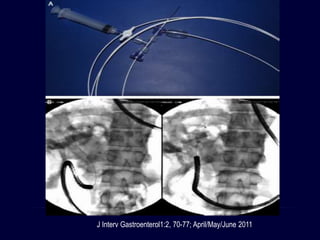

LITOTRIPSIA GUIADA POR

COLANGIOSCOPIO

• Colangioscopio madre y bebe

• Colangioscopio bebe tiene un canal de

instrumentación

• Litotriptor elctrohidráulico o laser

• Estudio multicéntrico de 10 centros en Estados

Unidos y 5 en Europa

• Eficacia del 71%

Gastrointest Endosc 2011; 74: 805-814

Gastroenterol Clin N Am 39 (2010) 209–227

J Interv Gastroenterol1:2, 70-77; April/May/June 2011

COLANGIOSCOPIA DIRECTA PERORAL

• Un endoscopio ultradelgado es maniobrado a través del esfínter

y dentro del ducto biliar

• Tiene muchas ventajas

• Mayor desventaja es atravesar el esfínter biliar y ganar acceso

al colédoco

• Larghi y Waxman: introducción de guia en la CPRE

• Presión manual sobre el abdomen

• Formación de asa en el estómago

World J Gastroenerol 2013 January 14; 19(2): 165-173

• Moon y cols: técnica con balón intraductal

• Avanzado por el conducto biliar intrahepático

• Difícil el retiro del balón

• Se ha reportado embolismo aereo

• Litotripsia: eficacia del 90%

• Promedio de 1,6 sesiones por paciente